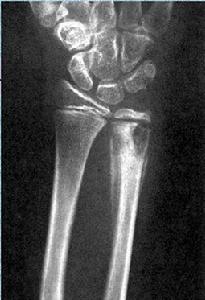

1.早期X線表現是海綿骨的骨質稀疏,繼而吸收消失,在骨內形成囊樣改變,由內向皮質侵蝕,因幼兒骨膜再生能力強,故使骨幹呈膨脹現象,稱為“骨氣臌”。

2.有時在其周圍可產生相當廣泛的平行層狀骨膜反應,使病骨更為增粗,形如紡錘,同時病骨周圍的軟組織亦有明顯腫脹。